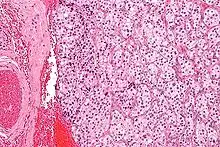

| Micrograph of a carotid body tumor (a type of paraganglioma). | |

On microscopic inspection, the tumor cells are readily recognized. Individual tumor cells are polygonal to oval and are arranged in distinctive cell balls, called Zellballen.[8] These cell balls are separated by fibrovascular stroma and surrounded by sustentacular cells.

With immunohistochemistry, the chief cells located in the cell balls are positive for chromogranin, synaptophysin, neuron specific enolase, serotonin, neurofilament and Neural cell adhesion molecule; they are S-100 protein negative. The sustentacular cells are S-100 positive and focally positive for glial fibrillary acidic protein. By histochemistry, the paraganglioma cells are argyrophilic, periodic acid Schiff negative, mucicarmine negative, and argentaffin negative.